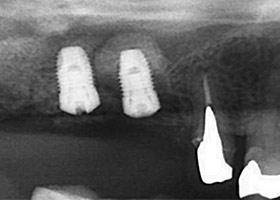

X光顯示垂直骨頭高度不足